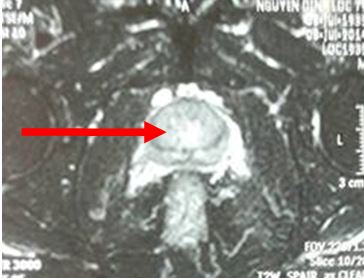

• MRI tiểu khung: khối u TLT chưa xâm lấn túi tinh

Hình ảnh MRI: khối u tuyến tiền liệt ranh giới không rõ, ngấm thuốc sau tiêm, kích thước 12 x 15 mm, chưa xâm lấn vỏ bao và túi tinh

• PSA: 2,4ng/ml

• Sinh thiết TLT qua đường trục tràng. Mô bệnh học: UTBM tuyến điểm Gleason 7

• Xạ hình xương; chưa di căn xương, CT ngực: bình thường

Chẩn đoán: Ung thư tuyến tiền liệt T2bNo Mo, có chỉ định cấy hạt phóng xạ

Tiến hành cấy hạt phóng xạ: 24 kim, tổng liều I-125: 145 Gy